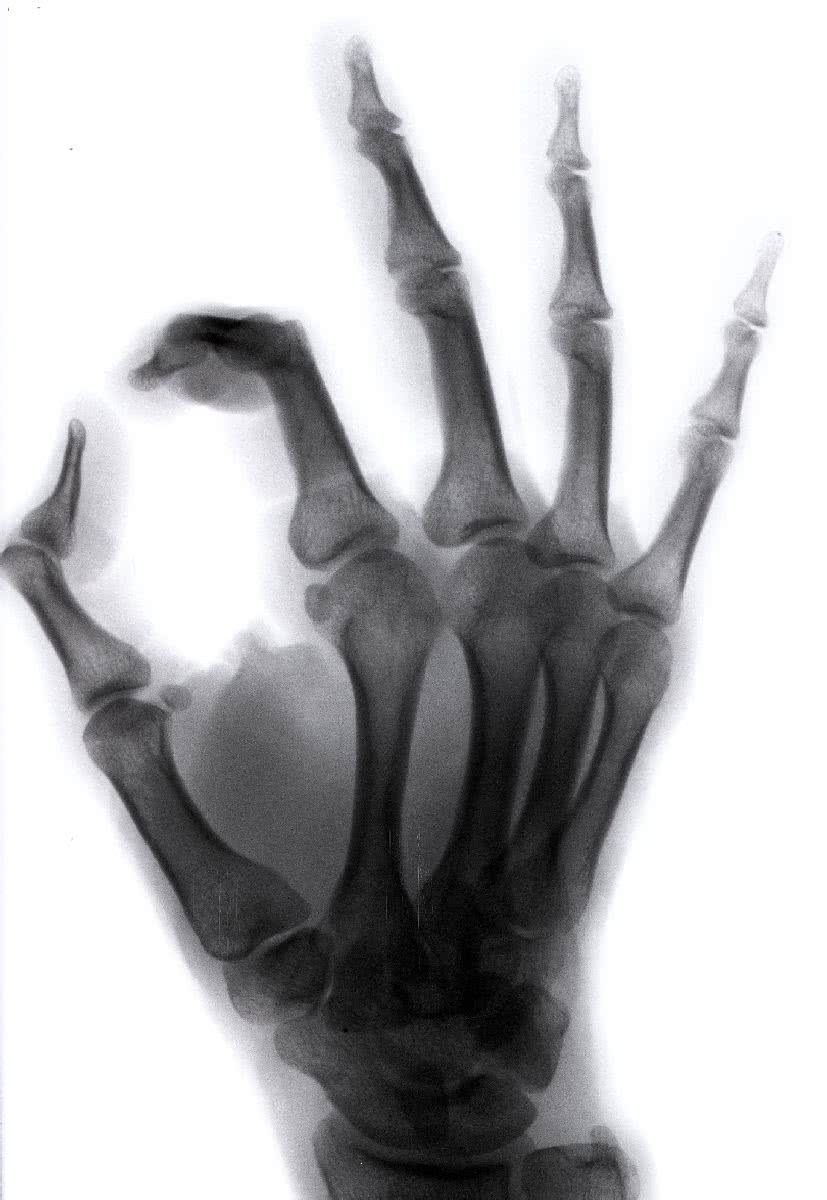

Kobiety w wieku pomenopauzalnym, które są zadowolone ze swojego życia, mają twardsze kości i są mniej narażone na osteoporozę, przekonują naukowcy.

Ubytek gęstości kości jest u tych kobiet o 52% mniejszy niż u tych, które nie są usatysfakcjonowane życiem.

Zmiany nastroju, zachodzące w trakcie 10 lat badań, miały także wpływ na poziom gęstości kości. Wśród kobiet, u których w ciągu dekady nasilały się nastroje depresyjne, gęstość kości zmniejszała się o 85% w porównaniu z tymi, które były nastawione optymistycznie, udowodniono podczas Kuopio Osteoporosis Risk Factor and Prevention Study, czyli badania czynników ryzyka i prewencji osteoporozy.

Wcześniejsze analizy dowodziły, że depresja ma negatywny wpływ na gęstość kości i prawdopodobieństwo wystąpienia osteoporozy, więc badacze chcieli się przekonać, czy w odwrotnej sytuacji jest podobnie. Przez 10 lat śledzili, w jaki sposób dobre samopoczucie może wpływać na gęstość kości 1147 kobiet.

Badanie potwierdziło, że pozytywne nastawienie do świata po okresie menopauzy pozwala osiągnąć większą gęstość naszej tkanki kostnej.